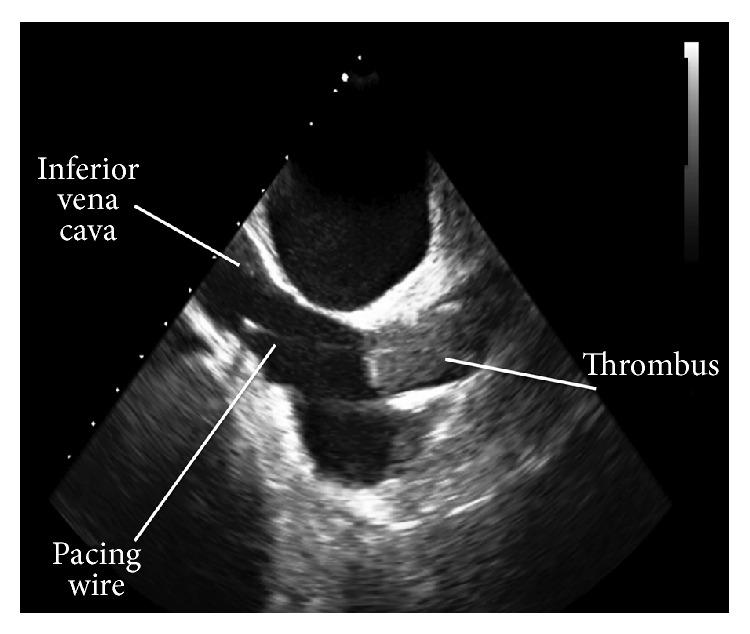

Three-dimensional (3D) echocardiography is becoming widely available and with novel applications. We report an interesting case of a 68-year-old lady with a central venous thrombosis coincident with both a dialysis catheter infection and a recent pacemaker insertion. Two-dimensional transesophageal echocardiography was unable to delineate whether the thrombosis was involved with the pacemaker wire or due to the tunneled catheter infection. The use of 3D echocardiography was able to produce distinct images aiding diagnosis. This circumvented the need for invasive investigations and inappropriate, high-risk removal of the pacing wire. This case highlights the emerging application of 3D echocardiography in routine nephrology practice.